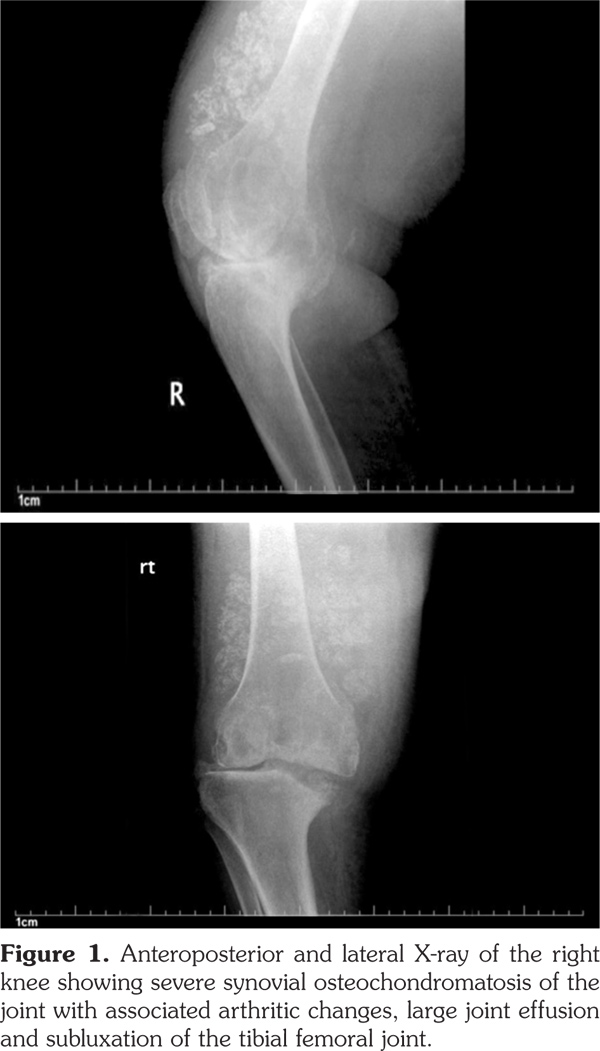

Plain radiographs of the knee joints revealed joint effusions with multiple rounded intra-articular loose bodies, erosions on the medial aspect of the tibial plateau, tricompartmental joint space narrowing, osteophytes, subchondral cyst formation, heterotopic bone formation, and lateral subluxation of the tibia on the femur (Figure 1, 2).

The patient was diagnosed with SOC, based on the presentation with chronic oligoarticular synovitis in the knees, and the X-ray findings. The consulting rheumatology and orthopedic services recommended conservative management due to the patient’s global health status, and in accordance with her wishes. The patient was subsequently transferred to a nursing home with instructions to use hinged knee braces.